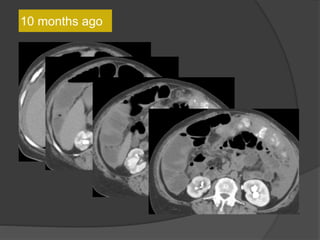

10 months ago

• Multilobulated thick-walled cystic lesion in the lesser sac and extending along the

adjacent peritoneal spaces and gastrohepatic ligament. Cystic lesion in the left

hemipelvis

• Minimal ascites, omental and mesenteric thickening

Present exam 15 days ago

Increased size

15 days

ago

Present exam

Case 1 Diagnosis: Recurrent metastatic disease

with mucinous ovarian tumor

15 days ago

7months ago